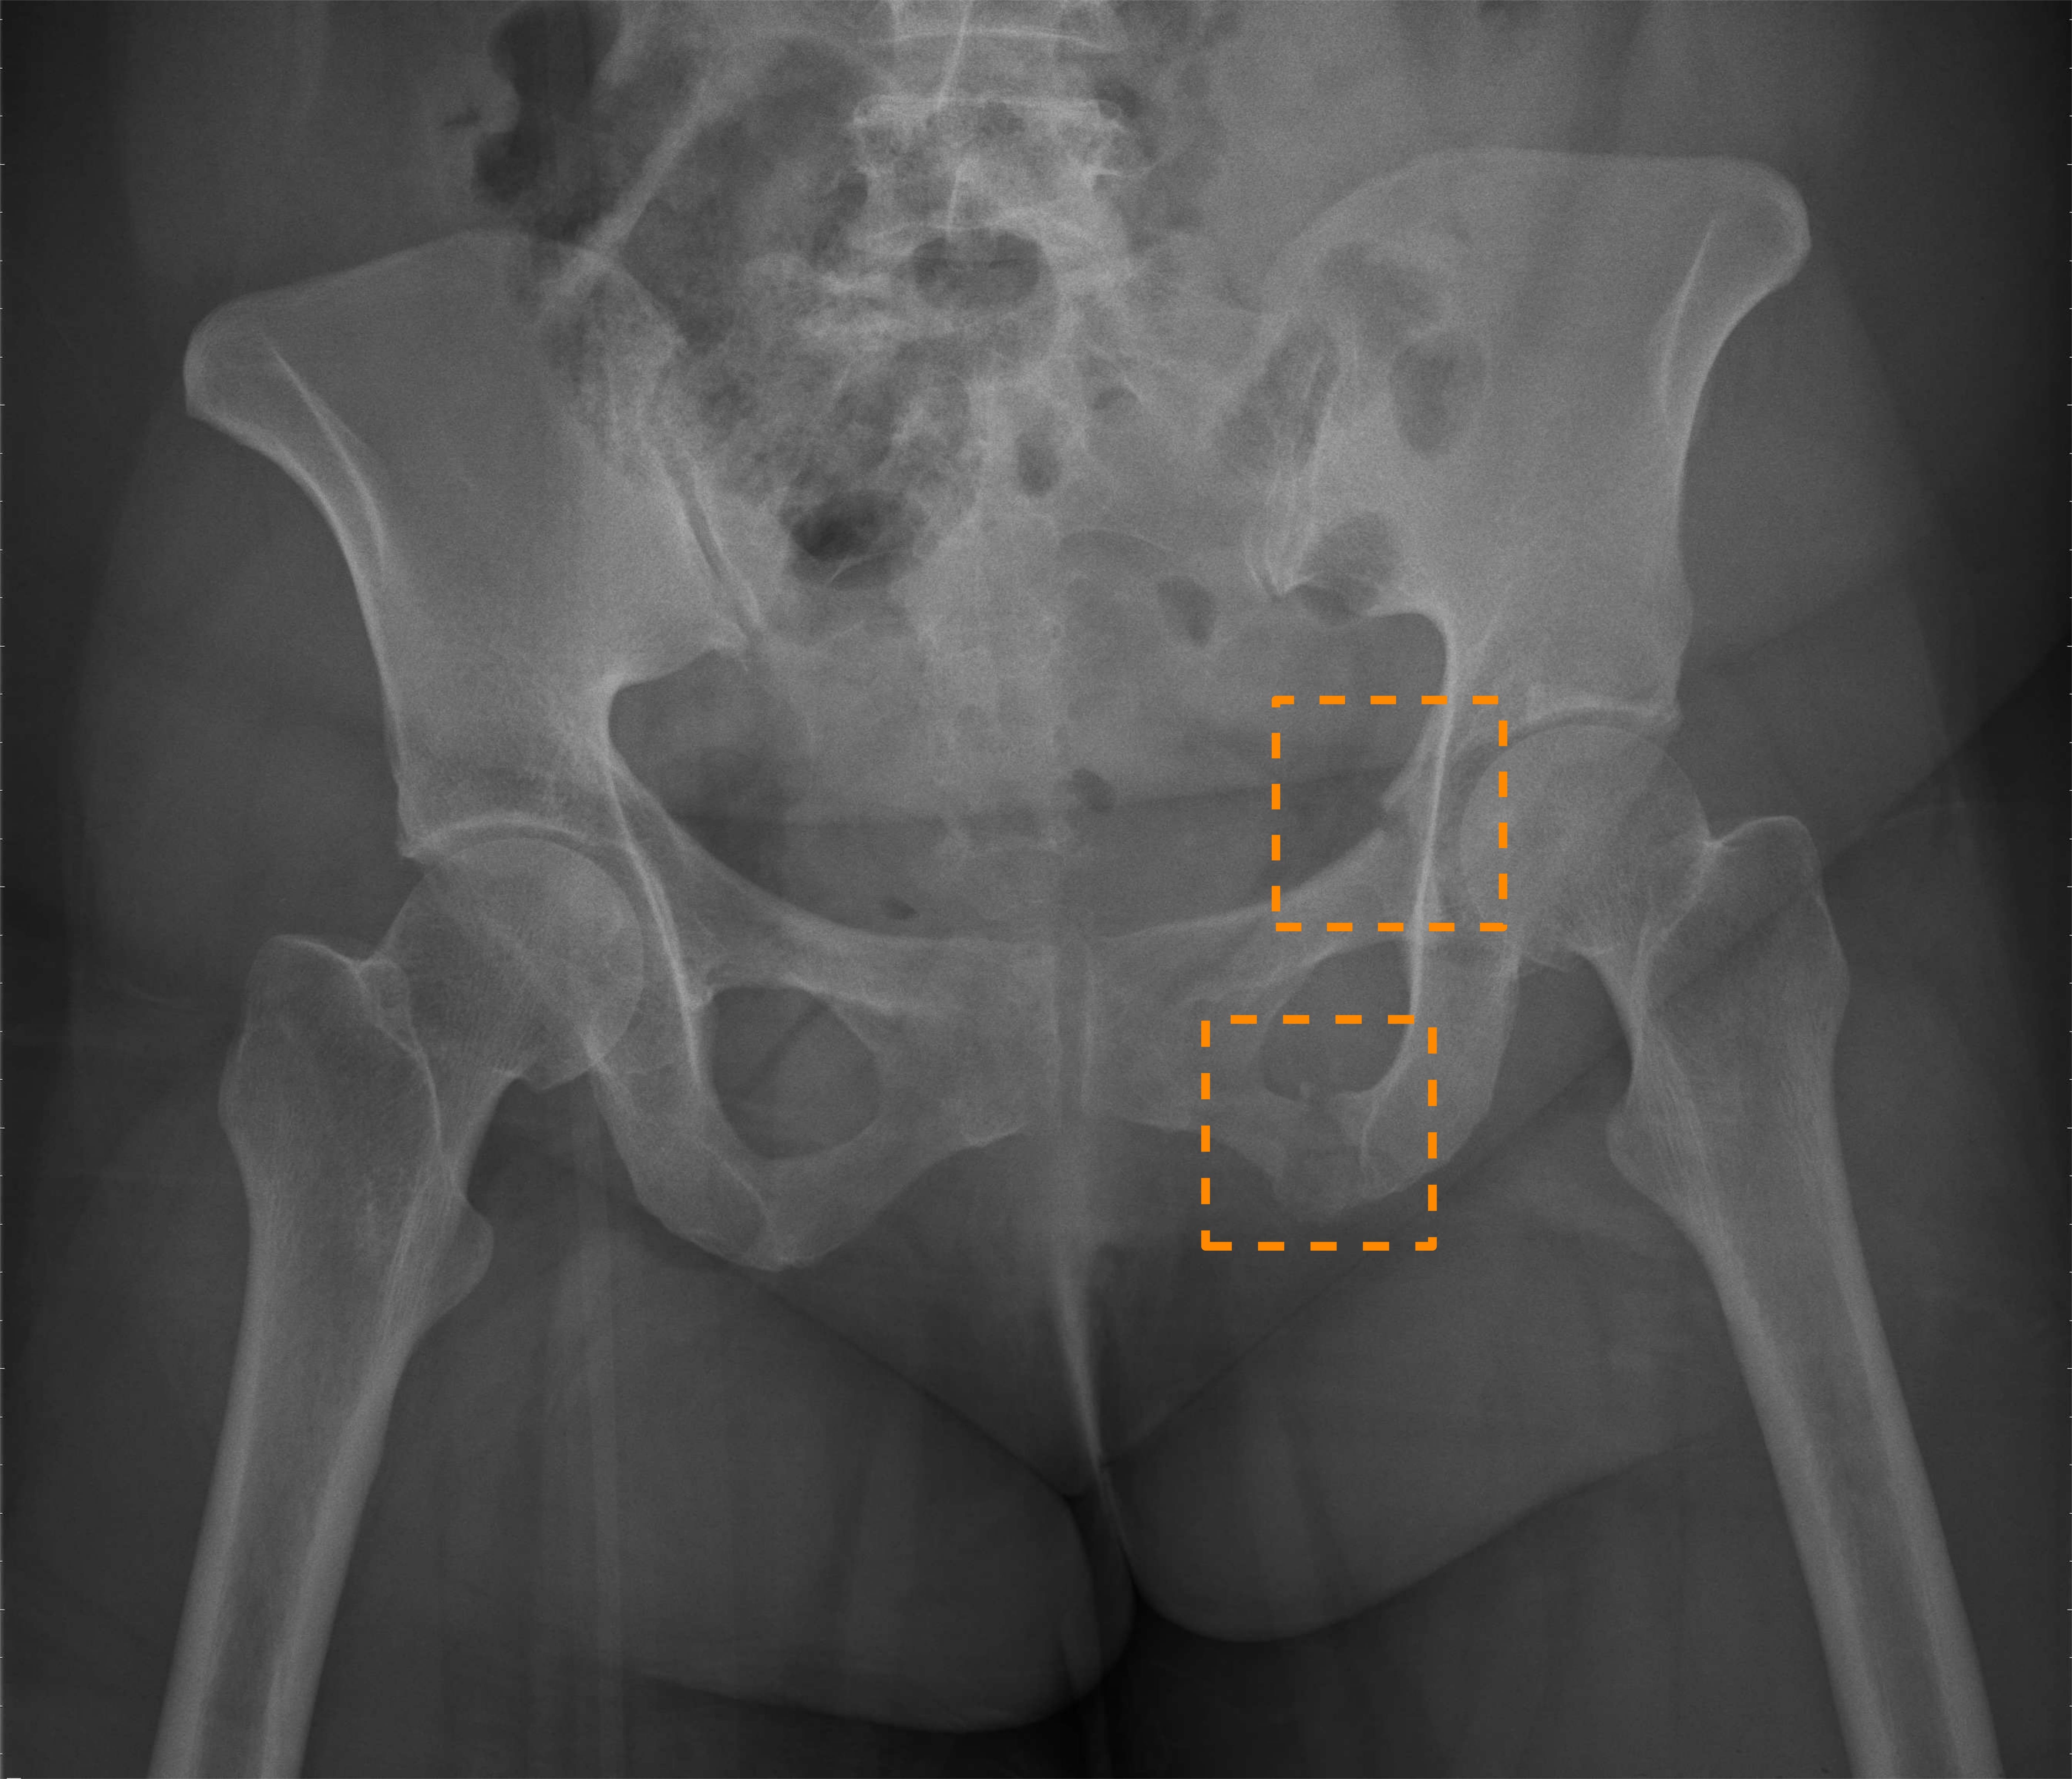

Refer to caption

Figure 1: Example \acPXR images of hip and pelvic fractures. (Left) Hip fracture. (Middle) Superior and inferior pubic ramus fracture. (Right) Iliac wing fracture.

Nonetheless, the above prior work all only focuses on diagnosing hip fractures and does not attempt to classify the more complex pelvic fractures (fractures in three pelvic bones: the ilium, ischium, and pubis). As Fig. 1 illustrates, the makeup of pelvis fractures is much more complex, as there are a large variety of possible types with very different visual patterns at various locations. In addition, pelvic bones overlap with the lower abdomen, further confounding image patterns. Finally, unlike hip fractures, which occur at the femoral neck/head, pelvic fractures can occur anywhere on the large pelvis, both increasing the aforementioned image pattern combinatorial complexity and precluding automatic \acROI extraction based on anatomy alone, such as was done in prior work [4]. Thus, while using \acROI-based classification is even more desirable for pelvic fractures, it is paradoxically more challenging to extract said \acpROI.